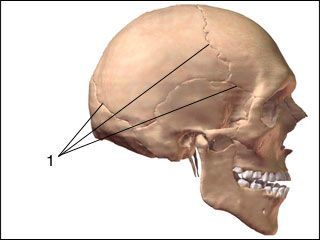

what type of jont does the arrow point to?

symphysis

syndesmosis

synostosis

synchondrosis

gomphosis

what type of jont does the arrow point to?

symphysis

syndesmosis

synostosis

synchondrosis

gomphosis

what is a synostosis fibrous joint? [1]

whats a bone with an example of a synostosis joint? [1]

what is a synostosis fibrous joint? [1]

At some sutures, the connective tissue will ossify and be converted into bone, causing the adjacent bones to fuse to each other (and make one big bone)

whats a bone with an example of a synostosis joint? [1]

frontal bone